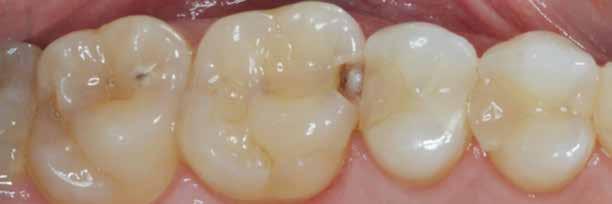

1. ábra: A restauráció peremének polírozása.

2. ábra: A páciens egy nem megfelelő I. osztályú ezüst-amalgám töméssel és II. osztályú szuvasodással jelentkezett. A fog izolálása kofferdám alkalmazásával történt.

3. ábra: A preparálás, a bondozás és a kompozit felvitele után. (Megjegyzés: némi kompozit túlfolyás látható a mesiális doboz axiális falain).

4. ábra: A durva finírozás után a restauráció pereme sima és anatómiailag is megfelelő.

Klinikai példa az 2–4. képeken látható.

6. ábra: I. osztályú restaurációk az első moláris és a második premoláris fogakban. A széleken felesleges kompozit figyelhető meg (piros nyilak jelölik).

7. ábra: A széleket durva szilikon polírozófejekkel finírozzuk.

A felesleges kompozit eltávolítását és a derékszögű záródási vonal kialakítását a 6–9. képek szemléltetik.

8. ábra: A durva finírozás után kialakult szélek.

9. ábra: Hat hónapos kontroll.